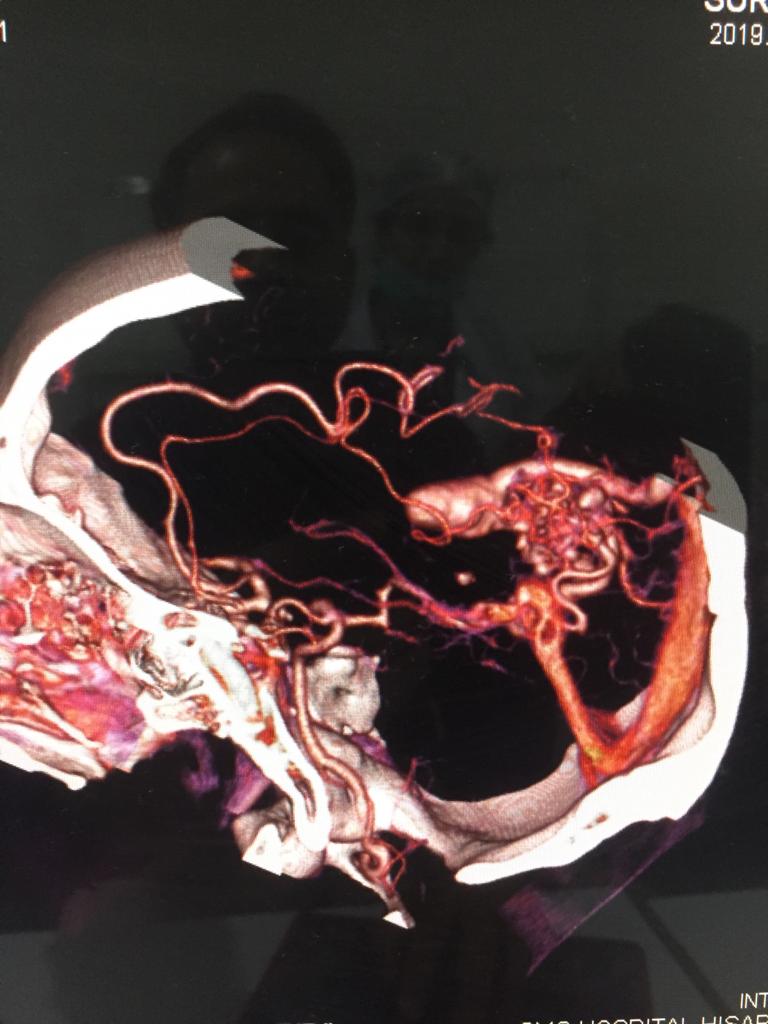

Cases